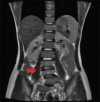

MURCS syndrome is a more severe form of Mayer-Rokitansky-Küster-Hauser (MRKH) syndrome, an acronym meaning aplasia/hypoplasia of Müllerian ducts (MU), congenital renal agenesis/ectopia (R), and cervical somite dysplasia (CS). A common presentation is primary amenorrhea in adolescent females. An anesthetist must consider the benefits and limitations of both regional and general anesthesia for these patients based on site of surgery and severity of malformations. We report successful anesthetic management of a 21-year-old female with MURCS syndrome scheduled for a creation of neovagina under spinal anesthesia using ultrasound guidance.